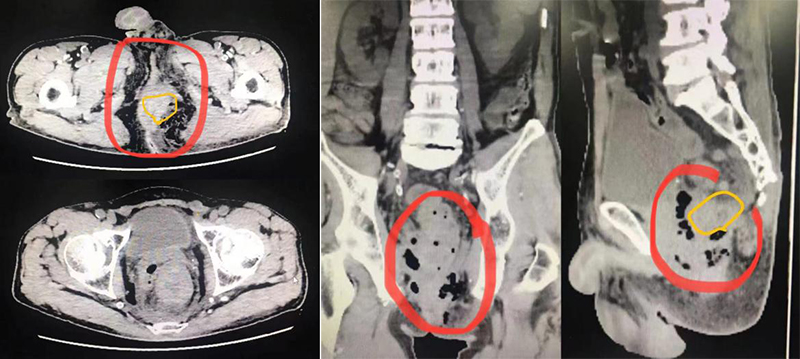

术前影像检查报告:红色范围黑色区域为皮下空腔,黄色范围包块为直肠肿瘤

在积极做好相关术前准备后,钟世彪带领医疗团队为张叔叔成功施行了腹腔镜下乙状结肠造口术+肛周坏死性筋膜炎清创术+直肠肿物活检术。术中可见直肠肿物距离肛门仅2cm,肛门左侧及左侧臀部红肿、质硬,皮下有一大小10cm*8cm的空腔,内分割形成许多小空腔并含脓液及积气,与右侧肛门相连。原来是肠肿瘤穿孔后肠内容物进入组织间隙引起的感染!